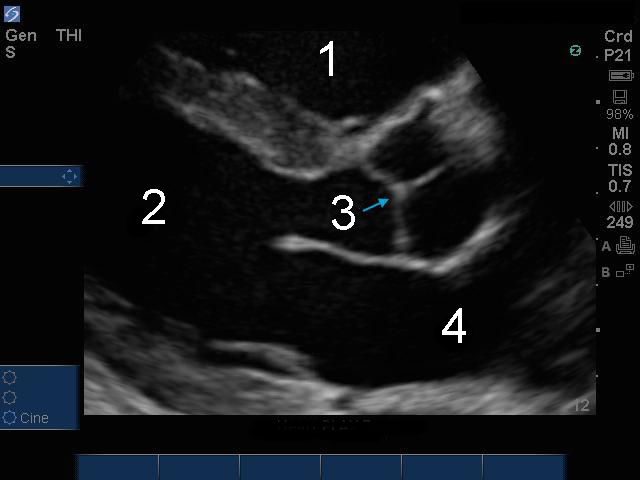

心臓 Parasternal Long Axis (PLAX)拡大画像

右心室 (RV)

左心室(LV)

大動脈弁 (AV)

左心房(LA)